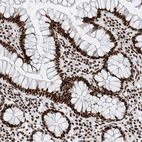

Immunohistochemical staining of human prostate shows strong nuclear positivity in glandular cells.